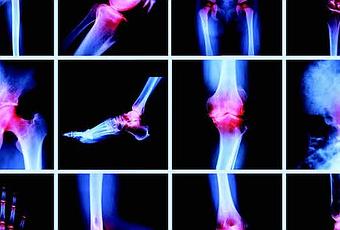

Escáneres de imagen y rayos X

Una radiografía o resonancia magnética de una articulación puede ayudar a un médico a identificar qué tipo de artritis está presente y monitorear el progreso de la AR a lo largo del tiempo.